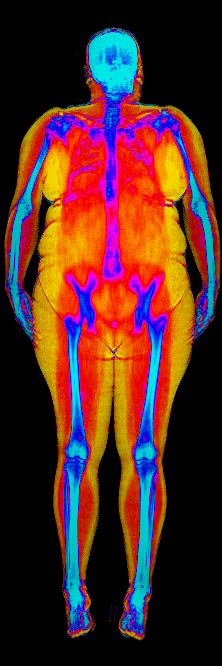

This page features real, anonymized DEXA scan images from BodyStats clients, organized by gender and body fat percentage in 5% increments. DEXA (Dual-Energy X-ray Absorptiometry) is the clinical gold standard for measuring body composition — far more accurate than scales, calipers, or visual estimates.

Each colorized scan shows the distribution of fat tissue (shown in warmer colors) and lean tissue (cooler colors) throughout the body. Compare your own DEXA scan to others in your range, or see what different body fat levels actually look like on a scan.

Female DEXA Scans by Body Fat %

35 to 40% body fat